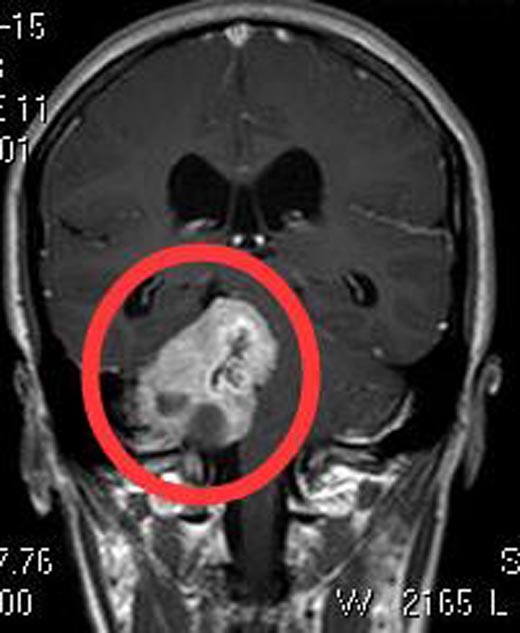

进一步头颅MR检查提示:右侧桥小脑角区囊实性占位性病变,大小约3.58cm×3.79cm×4.91cm,脑干及右侧桥臂受压变形。四脑室受压变窄,幕上脑室系统轻度扩张,考虑为听神经瘤。